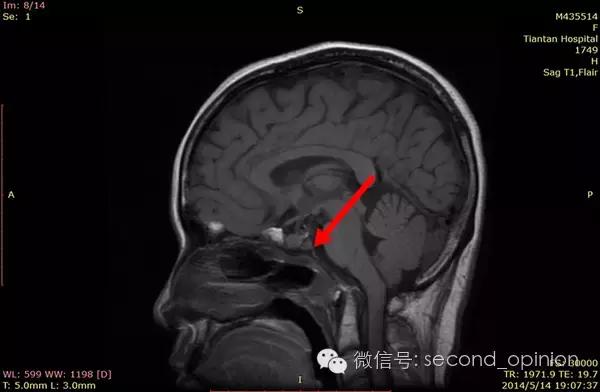

至2014年1月,出现左耳耳鸣,表现为低调杂音,未发现听力明显下降,偶有脸部麻木,无面瘫。行MRI检查,颅内占位范围约60*45*47mm。2014年2月2日第一次手术,行内镜导航下经蝶窦颅底肿瘤切除术,切除体积约50*45*50mm,手术顺利,术后头痛症状消失。左耳低调耳鸣术后消失两周后再次出现,右耳术后出现偶发轻度耳鸣。2014年5月4日第二次手术,行内镜口鼻蝶入路脊索瘤切除术,切除肿瘤体积45*40*50mm,过程顺利,术后耳鸣消失,病情稳定后出院。

2014年6月15日 进行射波刀放疗,32.5Gy/5fx,剂量曲线69%包绕,治疗期间对症脱水,减轻放疗反应,完成全部治疗后出院。

2014年12月 进行质子放射治疗。

日本国立癌症中心 2014年12月3日-12月31日

总剂量40GyE

2014年9月1日MRI(手术治疗前)

质子治疗前

2015年1月25日 对比质子治疗之前增强核磁共振影像无明显变化,脊索瘤放疗后变化缓慢,建议3月后继续复查。